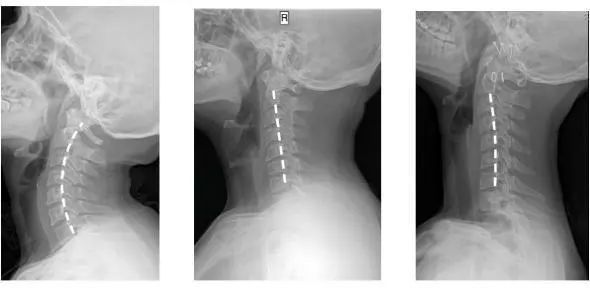

仰睡保持颈部「自然生理弯曲」

告别落枕,防治颈椎疾病

在中国,1.5亿人患有颈椎病

而90%的颈椎问题

都是因为

维持一个不正确的姿势时间太长引起的

人正常的颈椎是有弧度的

大约是前凸30-45°

但随着颈椎长时间承受着巨大压力

过于疲劳状态

于是弧度就

逐渐退化 变直 甚至反弓

第一张为正常生理曲度,第二张曲度变直,第三张是反向弯曲

前凸的颈椎曲度被改变

结果就是引发椎间盘突出

造成对血管和神经的压迫

肩膀和脖子容易酸痛僵硬

这已是颈椎病的初期症状